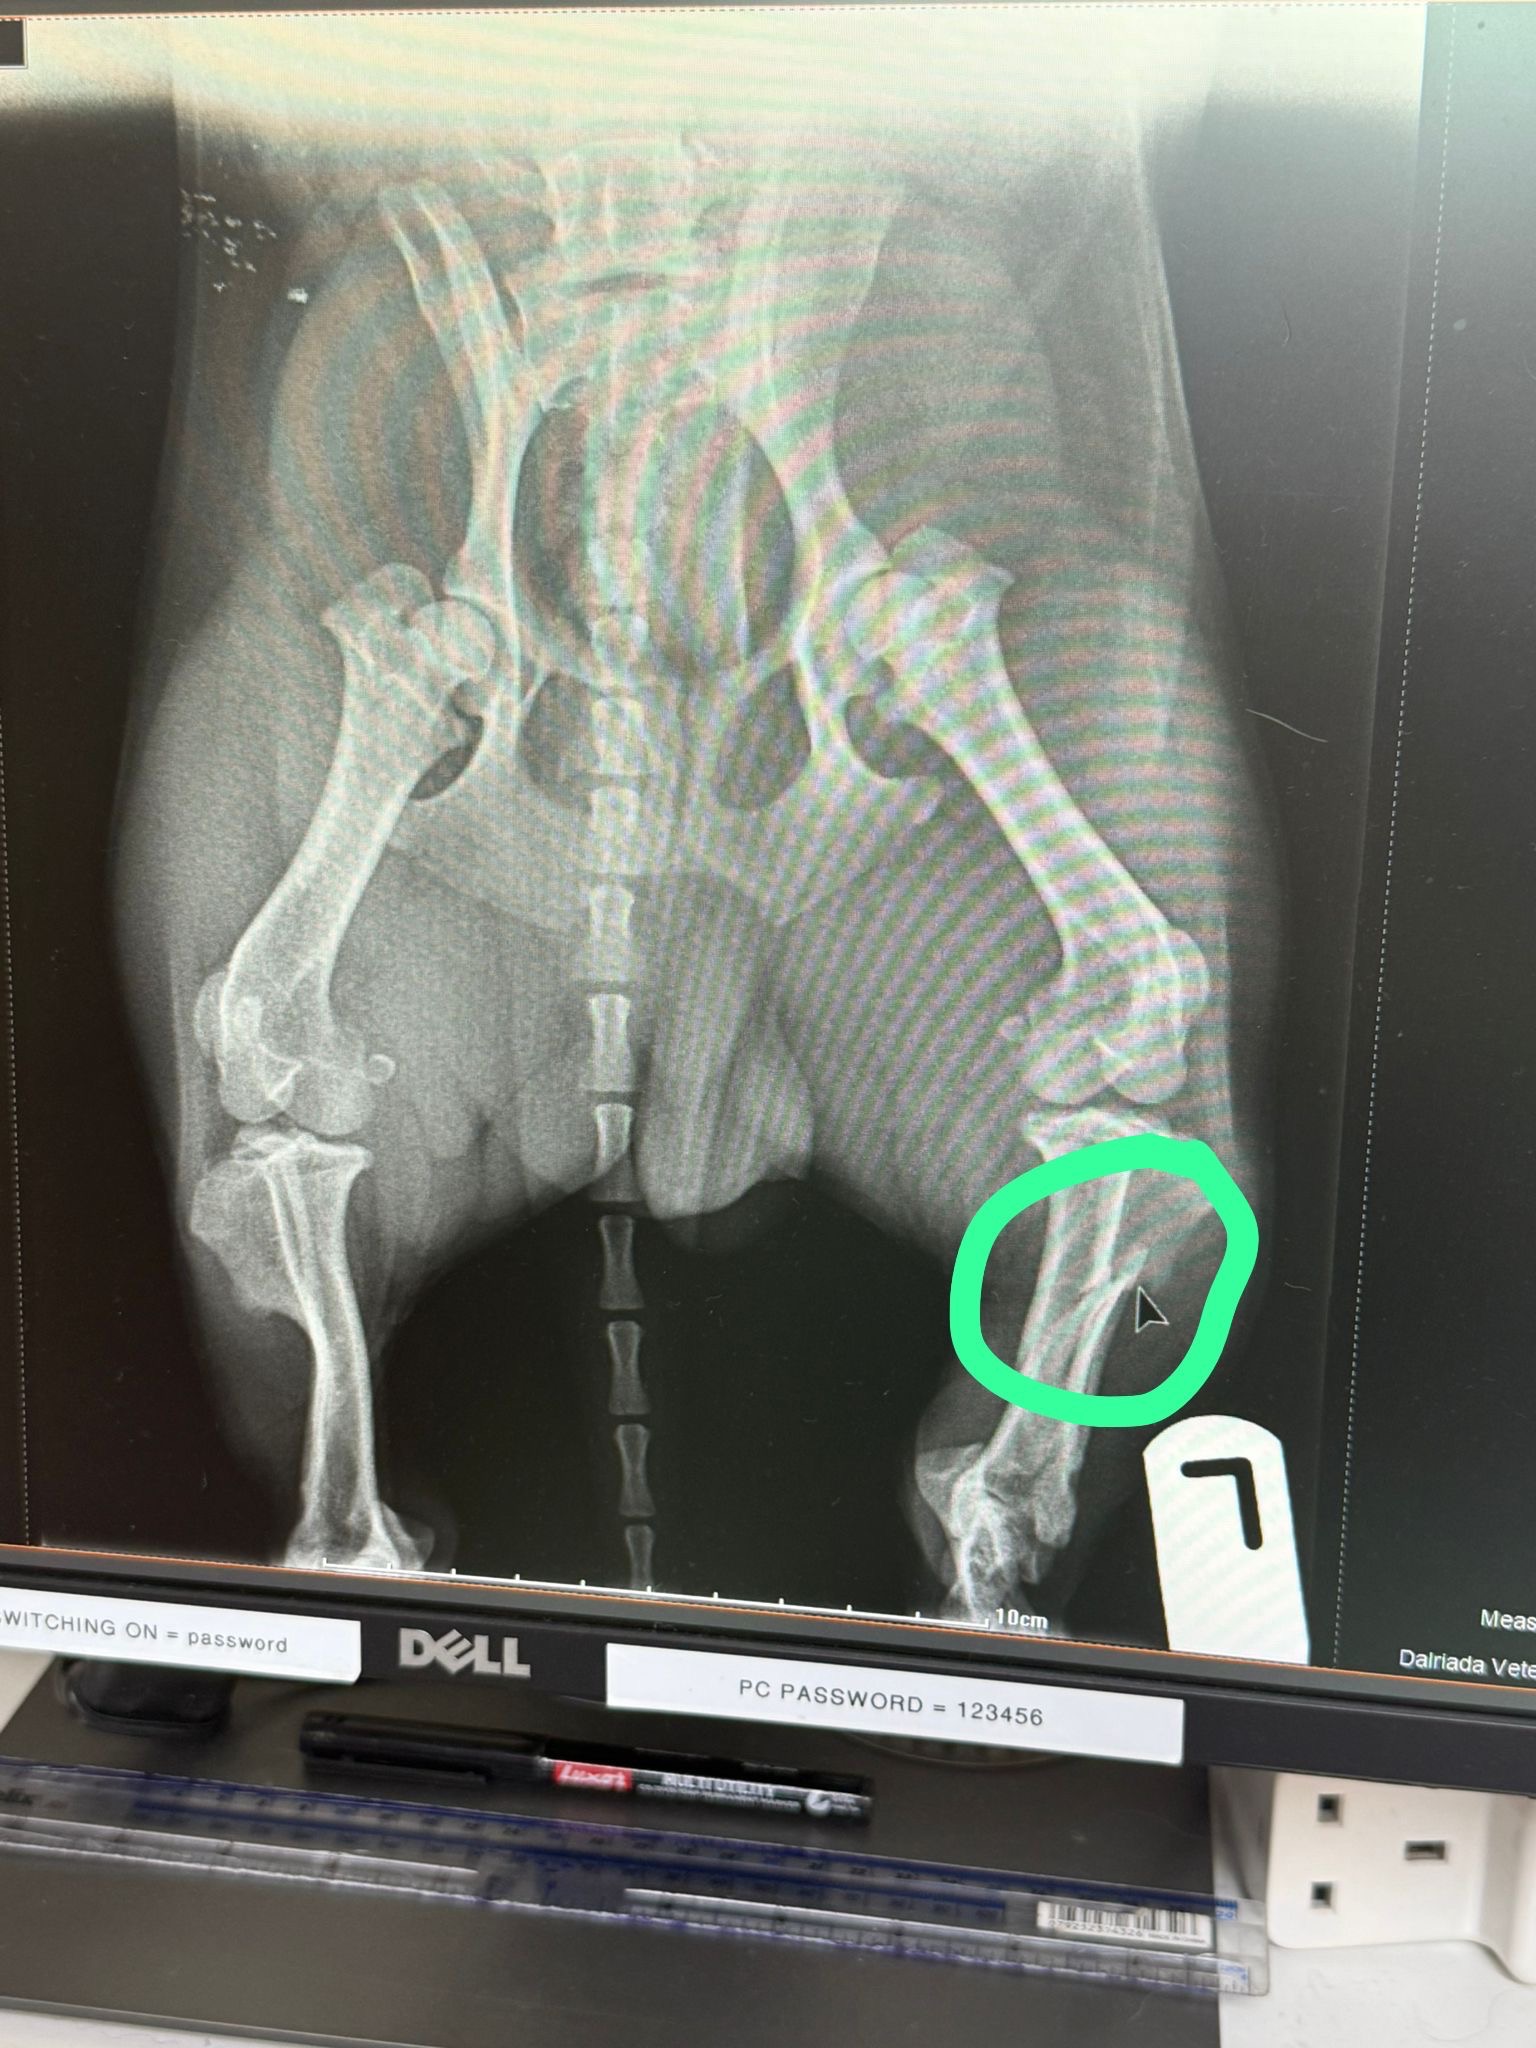

Hi my name is Jo and I am pleading for help, My daughter’s sausage dog Haggis has been run over. He needs an operation and already the cost since last night is spiralling. 3 X-rays Meds Anaesthetic, already 800 the Operation its self could be up to 4,000 and then the medication afterwards. Although Haggis was insured it was the basic package as my Daughter has 4 Children and of course never could have imagined this happening. My daughter is unable to work at the moment due to Lynne’s disease and all that has a knock on effect with lots of other ailment’s. She was a Soldier and moved to the Highland when she left the Army for a wonderful life for her self and children. They live an outdoor style of life, visiting other islands close to Oban. Haggis has become a huge part of that life and will need so much rehabilitation. My daughter and her children are overcoming a huge car crash not 3 months ago. The children have been traumatised through the incident. And now their wee puppy